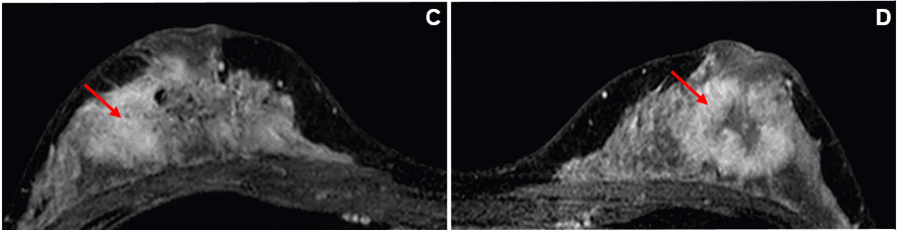

Approximately one year later, the patient returned with worsening bilateral breast pain and a new rapidly enlarging left breast mass. On exam, the inversion of her left NAC was similar to the right. The right-sided mass had increased with gross distortion of normal breast architecture. Ultrasound imaging and biopsy of the left retroareolar mass were also consistent with breast fibromatosis. (Figure 1B). MRI imaging of both breasts demonstrated progressive enhancement kinetics of the bilateral masses with non-enhancing cores consistent with fibrosis/fibrotic tissue (Figure 1C and Figure 1D). Neither tumor had involvement of the overlying skin or the chest wall.

C) MRI, axial view of the right breast with 5.2 × 4.9 × 2.6 cm irregular mass with involvement of nipple base to pectoralis fascia with notable nipple retraction. D) MRI, axial view of the left breast with 3.8 × 4.2 × 3.0 cm irregular mass with involvement of the nipple base to pectoralis fascia with notable nipple retraction.